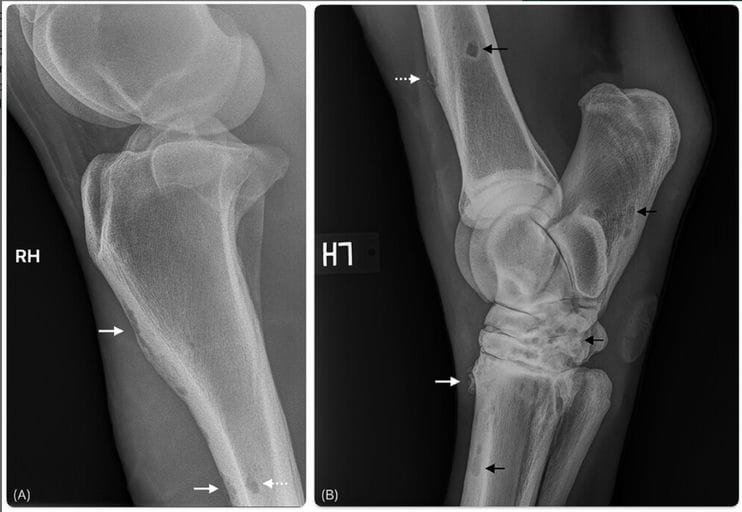

Initial radiographs revealed bilateral navicular degeneration and multiple discrete osteolytic lesions within the phalanges. Subsequent radiographs identified extensive polyostotic lytic lesions affecting multiple long bones, some associated with cortical thinning, expansion, and mild periosteal reaction. Post-mortem CT confirmed widespread osteolysis involving cortical, corticomedullary, and medullary regions of numerous bones. Histopathology demonstrated granulomatous inflammation composed of histiocytes, occasional multinucleated giant cells, and fibrous stroma replacing normal bone at sites corresponding to the radiographic and CT lesions. Necropsy also revealed widespread granulomatous disease affecting the skin, mesentery, peritoneum, skeletal muscle, colon, nervous system, and lymphatic tissues.

(A) Lateromedial radiograph of the right stifle (Agfa Healthcare, Musica Acquisition Workstation (NX), Belgium). Extensive cortical lysis along the cranial aspect of the proximal to mid-tibial diaphysis (solid white arrows), also superimposing with the trabecular cavity (dashed white arrow). (B) Lateromedial radiograph of the left tarsus. Lysis within the dorsal aspect of the distal tibial diaphysis results in expansion of the thinned cortex (dashed white arrow). Focal region of spiculated periosteal reaction along the proximal aspect of the third metatarsal bone (MTIII) (solid white arrow). Numerous additional rounded to ovoid and irregularly marginated lytic lesions within the distal tibia, calcaneus, tarsal bones, and proximal MTIII (black arrows).